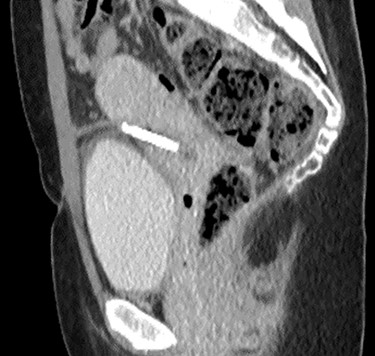

Computed tomography (CT) scan including a urographic phase revealed an IUCD in the vesico-uterine space, with one horn embedded into the bladder (Figs 2–4).

Sagittal CT urinary tract image demonstrating the device lying between uterus and bladder.